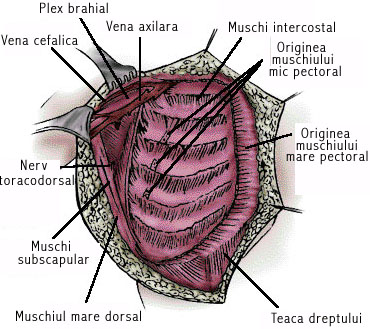

MASTECTOMII RADICALE - CHIRURGIE

MASTECTOMII RADICALE - CHIRURGIE I. DEFINITIE Mastectomiile radicale sunt operatiile care ridica sanul in totalitate, concomitent cu teritoriul limfatic aferent regional, ceea ce impune extirparea glandei mamare in intregime, in bloc cu teguCiteste tot ... 2574 cuvinte

Dimensiune medie

+ cu poze |